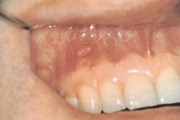

Kontaktist tekitatud kahjustused suulimaskestal

-Kontaktist põhjustatud mehhaanilist limaskesta kahjustust võivad esile kutsuda ortodontilised plaadid, breketid Harva põhjustavad kahjustusi täidismaterjalid.- Metalliärritust võivad anda breketid, aparaatide klambrid, hambakroonid – kroom, nikkel, berüllium, palladium, kloriid. Siia Loe edasi »